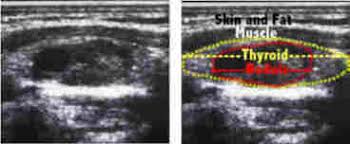

Ultrasonography Of The Thyroid Endotext Ncbi Bookshelf from www.ncbi.nlm.nih.gov A thyroid nodule can feel like a bump on the side or in the middle of the throat. Ultrasound is used to see the thyroid gland and the lymph node of the neck. Throat cancer is a condition that is characterized by the development of malignant tumors in the throat (pharynx), voice box (larynx) or tonsils. The cells are then looked at closely in the lab. In fact, the risk of cancer in any individual with thyroid nodules is. Some different types of cancers that can be detected. Throat cancer refers cancer that develops in your throat (pharynx) or voice box (larynx). Two in three cases of thyroid cancer occur in people under age 55, and 75%.

Can Ultrasound Detect Cancer New Health Advisor from www.newhealthadvisor.org If the cancer cells look like they might have come from the larynx or hypopharynx, an endoscopic exam and biopsy of these areas will be needed. Keep in mind, however, that an ultrasound alone cannot make the diagnosis of cancer. Throat cancer can develop in any part of the throat. So it doesn't mean cancer? A small device called a transducer is moved over the area. Thyroid nodules are lumps that can appear in the thyroid gland in front of the throat. Hashimoto's thyroiditis is an autoimmune disorder in which our body produces antibodies against the thyroid causing the thyroid to become inflamed and damaged. What does ovarian cancer look like on an ultrasound is not an easy question to answer.